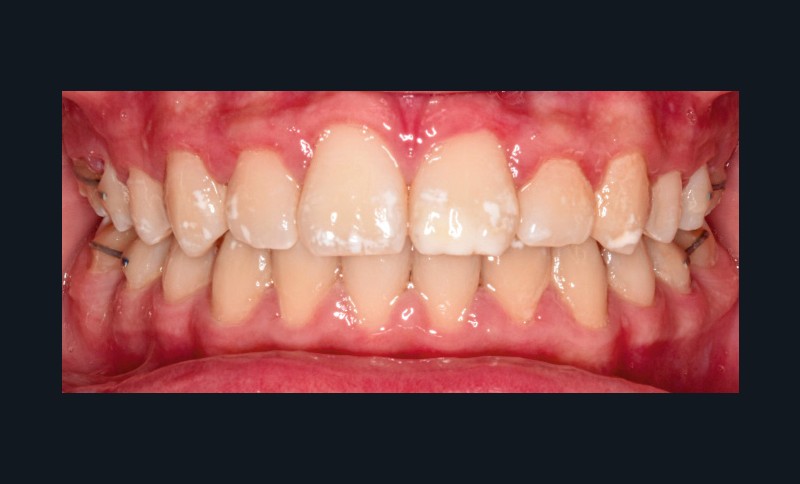

L’examen clinique montre une MIH sévère sur 16, 26, 36 et 46, et modérée sur 11 et 21.

Sur le plan esthétique : profil orthofrontal, visage équilibré (fig. 1a).

Sur le plan alvéolo-dentaire (fig. 1b) :

- Classe II subdivision gauche avec déviation du point inter-incisif mandibulaire à gauche ;

- occlusion inversée entre 22 et 32 ;

- dysharmonie dento-arcade (DDA) sévère ;

- 13 en position haute retenue.